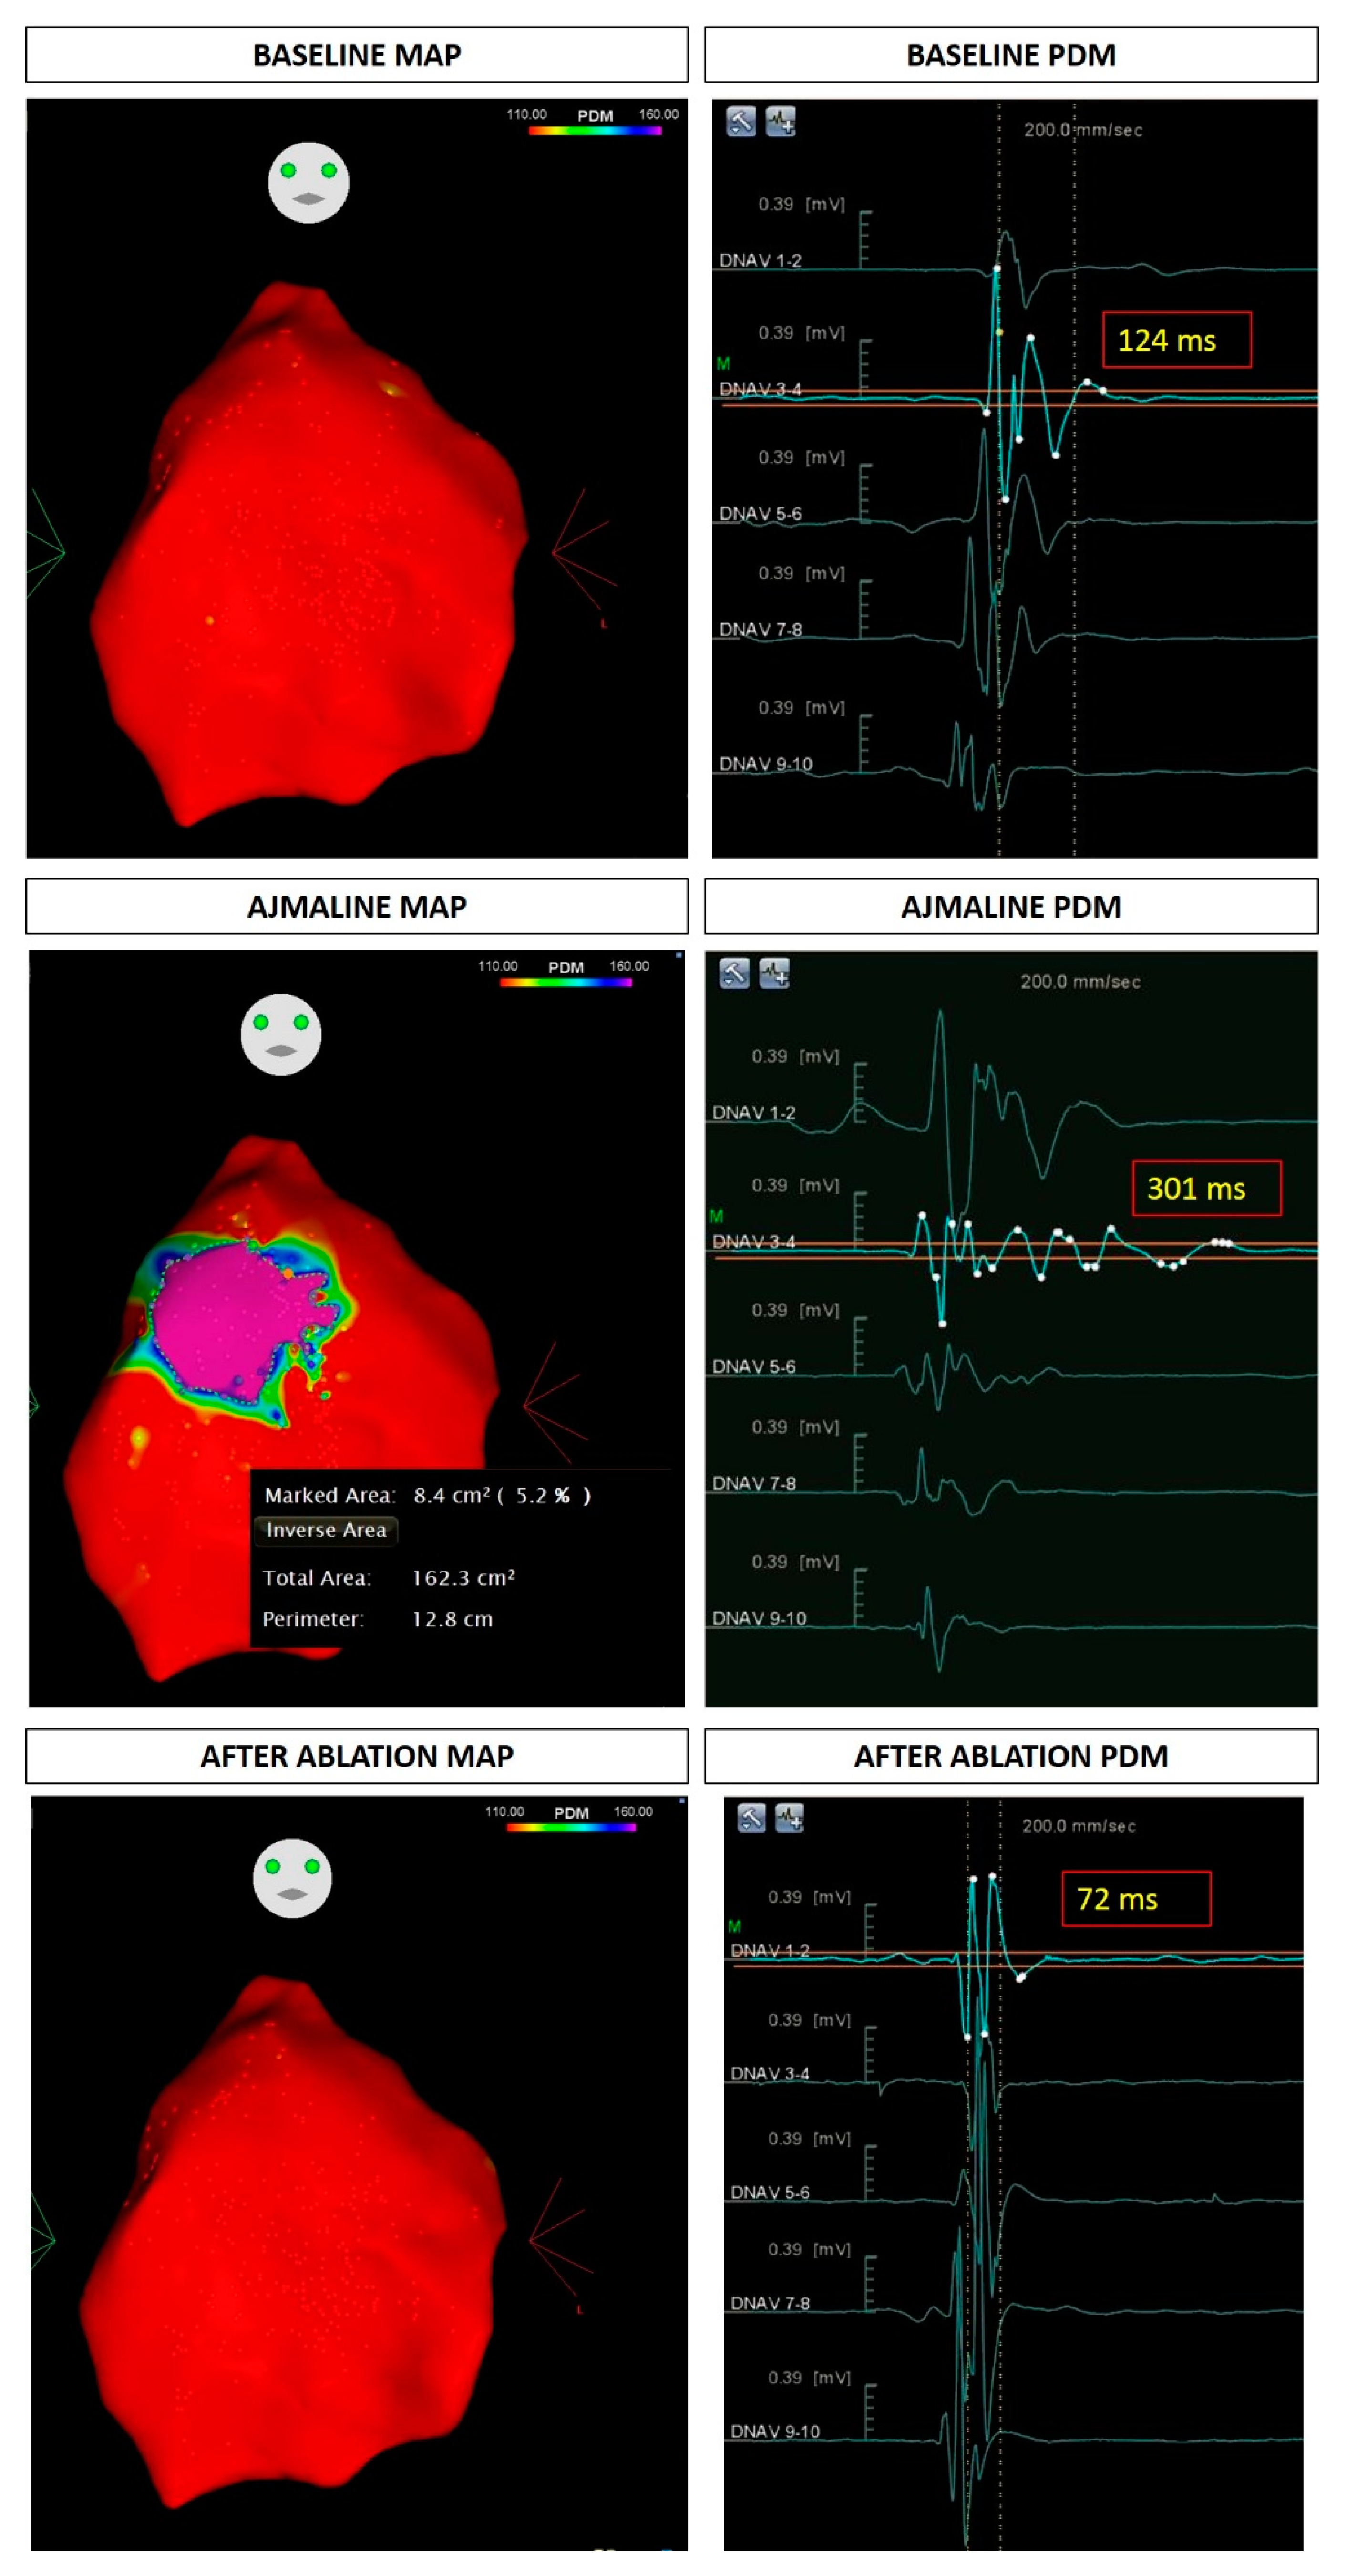

- Pappone, C.; Brugada, J.; Vicedomini, G.; Ciconte, G.; Manguso, F.; Saviano, M.; Vitale, R.; Cuko, A.; Giannelli, L.; Calovic, Z.; et al. Electrical Substrate Elimination in 135 Consecutive Patients with Brugada Syndrome. Circ. Arrhythm. Electrophysiol. 2017, 10, e005053. [Google Scholar] [CrossRef]